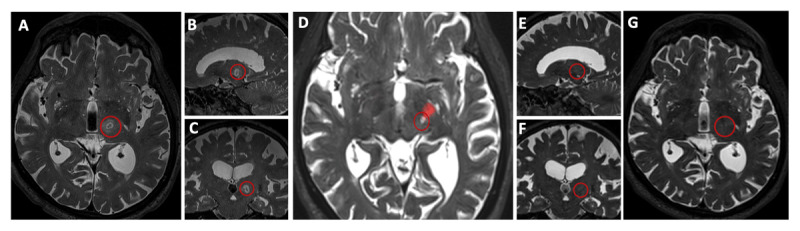

Case report: An 86-year-old man with refractory ET underwent MRgFUS thalamotomy. Tremor improved by 95% and remained controlled until his death 35 months later. Postmortem MRI and neuropathologic analysis showed localized disruption of the dentatorubrothalamic tract and demyelination near the treatment site with preserved neuronal integrity.

Discussion: This is the first postmortem analysis of MRgFUS thalamotomy 35 months after procedure. Findings confirm sustained tremor relief associated with selective demyelination. The lesion remained well-defined without expansion, supporting MRgFUS as a precise and safe treatment for ET.

Highlights: This paper presents the first long-term (35-month) postmortem analysis of MRgFUS thalamotomy demonstrating sustained clinical efficacy. Postmortem MRI confirmed that the lesion remained localized to the original thalamotomy site, with focal disruption of the dentatorubrothalamic tract. Neuropathological examination revealed selective demyelination in the posterior thalamus near the treatment site, without evidence of neuronal loss. These findings support the long-term safety, precision, and durability of MRgFUS as a non-invasive therapeutic option for essential tremor.